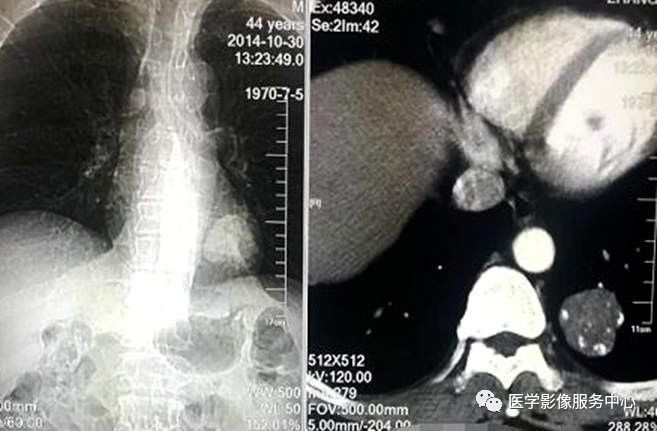

胸部CT平扫

胸部CT增强

CT表现:左肺下叶不规则肿块影,内见脂肪密度及多发钙化,增强扫描未见明显强化,纵隔未见肿大淋巴结。